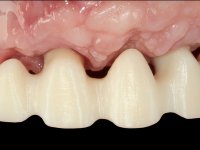

10 weeks after the surgery, a first impression was done to do a CAD-CAM provisional bridge (based on the diagnostic wax-up), that worked the soft tissue architecture during two months. This architecture was copied in a second impression by individualizing the impression copings in their emerging profile.

The bridge was finally placed with a progressive screwing to allow the tissue to accommodate the pressure of the pontics and the abutments emergency profiles.